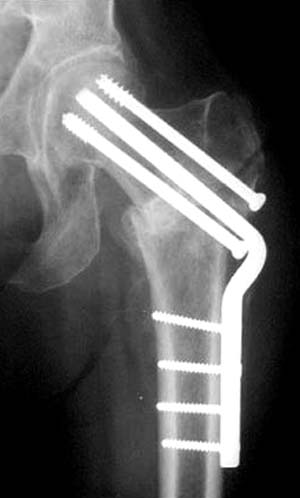

Для убедительности здесь пример подвертельного перелома после 3 недели, где латеральный кортекс ослаблен еще и из-за неоднократных попыток введения шурупов.

>Винты немного вертикальнее провести и было бы красивее

Правильная техника фиксации - это три параллельных каннюлированных винта под углом 130 -135 градусов к диафизу, не ниже уровня малого вертеля. Проведенные ниже вертела винты с бОльшим углом (более вертикальные) в 20% осложнялись подвертельными переломами бедра. Ближе к кортикальному слою винты с длинным контактом резбовой части, а также каннюлирванные механически лучше, чем сплошные. Расположение винтово - в в виде V т.е. один внизу по калькару и два сверху-спереди и сзади.